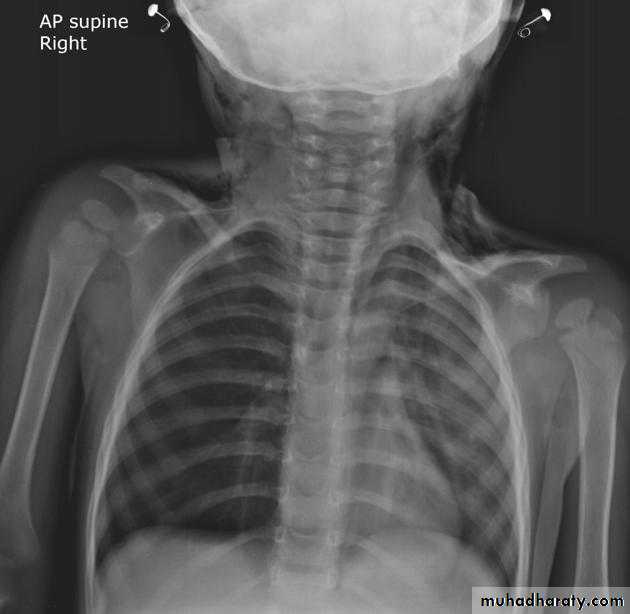

Plain radiographChest radiographs are the most commonly used examination to assess for presence of a pleural effusion, however it should be noted that on a routine erect chest x-ray as much as 250-600 ml of fluid is required before it becomes evident 6. A lateral decubitus film is most sensitive, able to identify even a small amount of fluid. At the other extreme, supine films can mask large quantities of fluid.

A lateral decubitus film (obtained with the patient lying on their side, effusion side down, with a cross table shoot through technique) can visualise small amounts of fluid layering against the dependent parietal pleura.